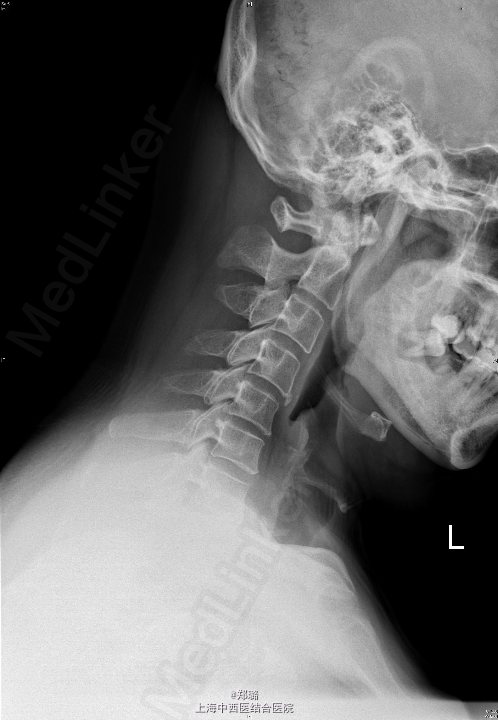

查体:神志清晰,精神尚可,呼吸平稳,营养中等,表情自如,发育正常,自主体位,应答流畅,查体合作。全身皮肤无黄染,无肝掌、蜘蛛痣。全身浅表淋巴结无肿大。脊柱无畸形,生理曲度变直,压颈试验(+),臂丛牵拉试验(+),右肩颈部疼痛,右上臂、前臂桡侧、手部刺痛觉迟钝,双Hoffmann征(-),双侧Babinski征(-);双侧Chaddock征(-),双侧肱二头肌腱膜反射可疑亢进,双侧膝反射正常,四肢肌力尚可。 辅助检查: 外院:CT及MRI(2015-5-19)示:C5/6椎间盘突出,C4/5椎间盘轻度突出 颈椎过伸过屈侧位X线【2015-05-22】 :颈椎动力位未见明显椎体滑脱征象。 颈椎正位(前后位)、侧位X线【2015-05-22】 :颈椎退行性变